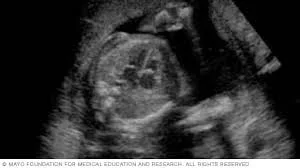

• Semana 24

Semana 24

El feto mide entre 21 y 22 cm y pesa unos 600 gramos. Los pulmones siguen desarrollándose, pero todavía no son completamente funcionales. El sistema nervioso está lo suficientemente desarrollado para controlar algunos movimientos reflejos. La piel del feto es delgada y traslúcida, pero sigue acumulando grasa bajo la piel para prepararse para el nacimiento.